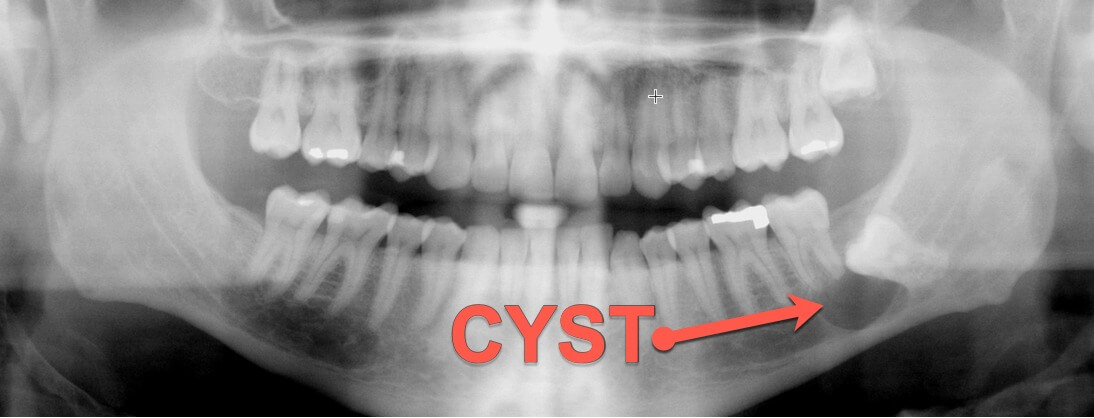

- Diagnose abnormal cysts, abscesses or other growths – x-rays can catch these problems before they grow, weaken the jaw and do damage to nearby teeth.